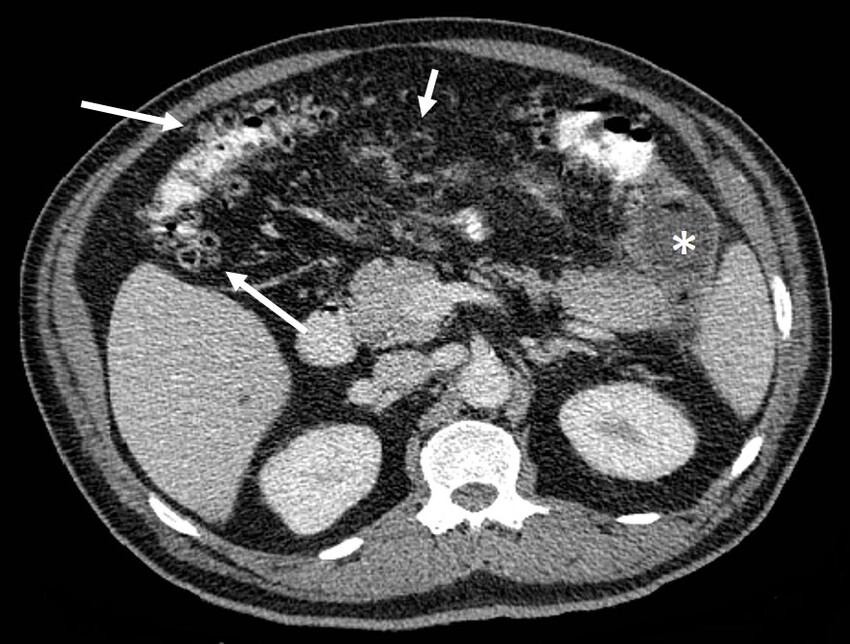

Se le realizó ultrasonido hepatobiliopancreático, en el que no se observaron alteraciones en el páncreas ni cálculos en la vesícula biliar. Por sospecha de diverticulitis, se le realizó TC de abdomen con contraste oral e intravenoso, evidenciándose una gran cantidad de divertículos en todo el marco colónico, con una colección líquida en contacto con la pared del colon, a nivel del ángulo esplénico (Fig. 1). Además, se observó una marcada estriación de la grasa mesentérica, con mínima cantidad de líquido interasa. Estos hallazgos fueron diagnósticos de diverticulitis aguda complicada. La colección en mención se encontraba en estrecho contacto con la cola del páncreas, lo que explicaría la elevación en las enzimas pancreáticas, debido a cambios inflamatorios por contigüidad.